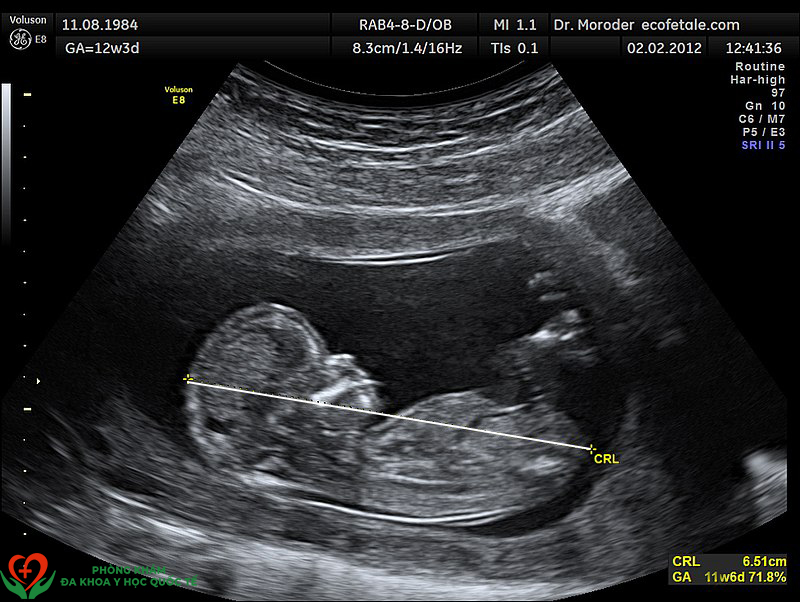

Tuần thứ 11 của thai kỳ (tương đương tuần thứ 9 sau thụ tinh) nằm trong ba tháng đầu tiên của thai kỳ, và đây là thời điểm em bé chính thức được miêu tả bằng từ "thai". Thai nhi 11 tuần tuổi phát triển rất nhanh, ngoại hình đã có hình dạng đặc trưng của loài người.

Đầu thai nhi có độ dài bằng khoảng một nửa tổng chiều dài của thai nhi, phần thân bắt đầu phát triển nhanh chóng. Khuôn mặt của thai nhi rộng ra, hai mắt tách xa nhau, mí mắt nhắm lại. Tai đã gần đạt được hình dạng cuối cùng, mũi đã xuất hiện đường khí đạo, trong miệng đã hình thành lưỡi và hàm ếch, mầm răng tương lai xuất hiện. Núm vú có thể nhìn thấy được. Tay và chân ở phía trước của cơ thể, không còn hình dạng mái chèo nữa, mà các ngón tay và ngón chân đã xuất hiện. Hồng cầu bắt đầu hình thành trong gan thai nhi. Đến cuối tuần thứ 11, bộ phận sinh dục ngoài bắt đầu phát triển.

Chiều dài thai nhi giai đoạn này khoảng 41mm (1.6inch) và nặng khoảng 45g (0.03 ounce). Mẹ bầu giai đoạn này sẽ thắc mắc thai nhi 11 tuần biết làm gì và khá nhạy cảm với từng cử động của em bé, mặc dù không cảm nhận được thai máy do kích thước thai nhi còn quá nhỏ.

Để phát hiện sớm hội chứng Down ở thai nhi, bác sĩ có thể siêu âm đo độ mờ da gáy của thai nhi vào tuần thứ 11 thai kỳ. Độ mờ da gáy được xác định chính xác nhất trong khoảng thời gian từ tuần 11 đến tuần 13 tuần 6 ngày. Nếu tiến hành siêu âm quá sớm, kết quả sẽ không chính xác vì lúc này thai nhi còn quá nhỏ. Còn nếu quá muộn, thì kết quả cũng sẽ không còn ý nghĩa.